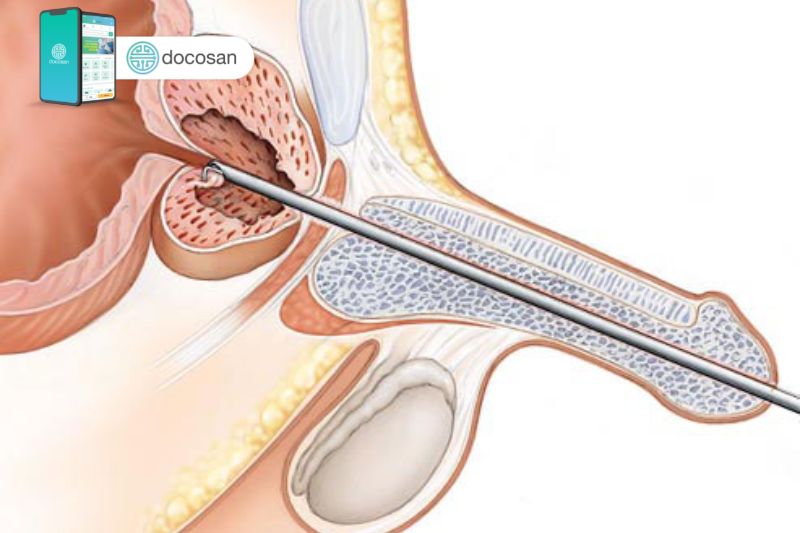

U phì đại tiền liệt tuyến là một bệnh lý nam khoa phổ biến ở người đàn ông trung niên hoặc lớn tuổi. Bệnh còn được gọi là u phì đại lành tính tuyến tiền liệt và có thể gây ra các triệu chứng tiết niệu khó chịu khi kích thước u quá lớn. Nếu người bệnh không được điều trị, u phì đại tiền liệt tuyến có thể gây tắc nghẽn đến hoàn toàn dòng nước tiểu của niệu đạo và từ đó gây vấn đề cho bàng quang, tiết niệu và cả thận.

Tiền liệt tuyến là cơ quan sinh dục của nam giới có vai trò sản xuất hầu hết các chất có trong tinh dịch, từ đó làm chất dịch màu trắng sữa nuôi dưỡng và vận chuyển tinh trùng khi xuất tinh. Vị trí nằm bên dưới bàng quang và tiếp xúc trực tiếp với ống vận chuyển nước tiểu từ bàng quang sẽ đi qua trung tâm của tiền liệt tuyến.

Hầu hết nam giới sẽ được tiếp tục tăng trưởng tiền liệt tuyến trong suốt cuộc đời và sự tăng trưởng này trực tiếp gây ra u phì đại tiền liệt tuyến. Nếu kích thước u đủ lớn và gây chèn ép sẽ gây ra các triệu chứng tiết niệu do gây tắc nghẽn đáng kể lưu lượng nước tiểu. Các bác sĩ nam khoa không chắc chắn chính xác nguyên nhân làm cho tiền liệt tuyến ngày càng to ra, có thể là do những biến đổi sự cân bằng của hormone sinh dục nam của người lớn tuổi.

U phì đại tiền liệt tuyến gây bí tiểu mạn tính

Bí tiểu là biến chứng thường gặp của bệnh nhân bị u xơ tiền liệt tuyến vì u xơ phì đại quá mức sẽ làm tắc nghẽn ống tiểu của nam giới. Đi kèm với triệu chứng bí tiểu, nam giới còn tăng nguy cơ bị chứng tiểu buốt, tiểu đau và tiểu ra máu. Từ đó lần nào đi tiểu cũng dần trở thành ám ảnh của người đàn ông.